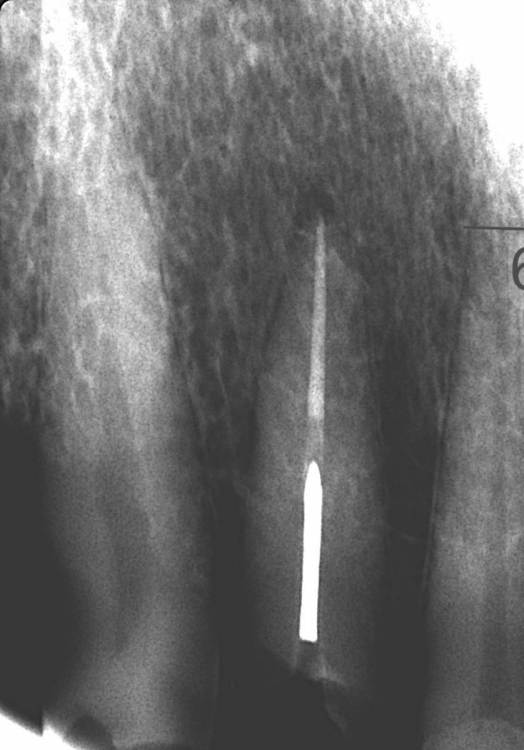

GENRY Опубликовано 28 сентября, 2023 Автор Поделиться Опубликовано 28 сентября, 2023 Моя история еще не закончилась. Для тех, кто попал в аналогичную ситуацию, выкладываю промежуточные результаты: Снимок 1- обломок вкв извлечен, канал перелечен. Под микроскопом, с помощью ультразвука. Снимок 2- вставлена ВКВ из кобальт хромового сплава. Снимок 3 - вид снаружи на еще неошлифованную ВКВ. Пока все вроде нормально, но риски остаются. Следует пройти 30 дневный этап носки временной пласмассовой коронки для формирования дисневого края перед установкой постоянной диоксид циркониевой коронки. Есть вопросы по протезированию...но думаю их лучше задать в соответствующем разделе. Спасибо всем за советы и участие! Ссылка на комментарий